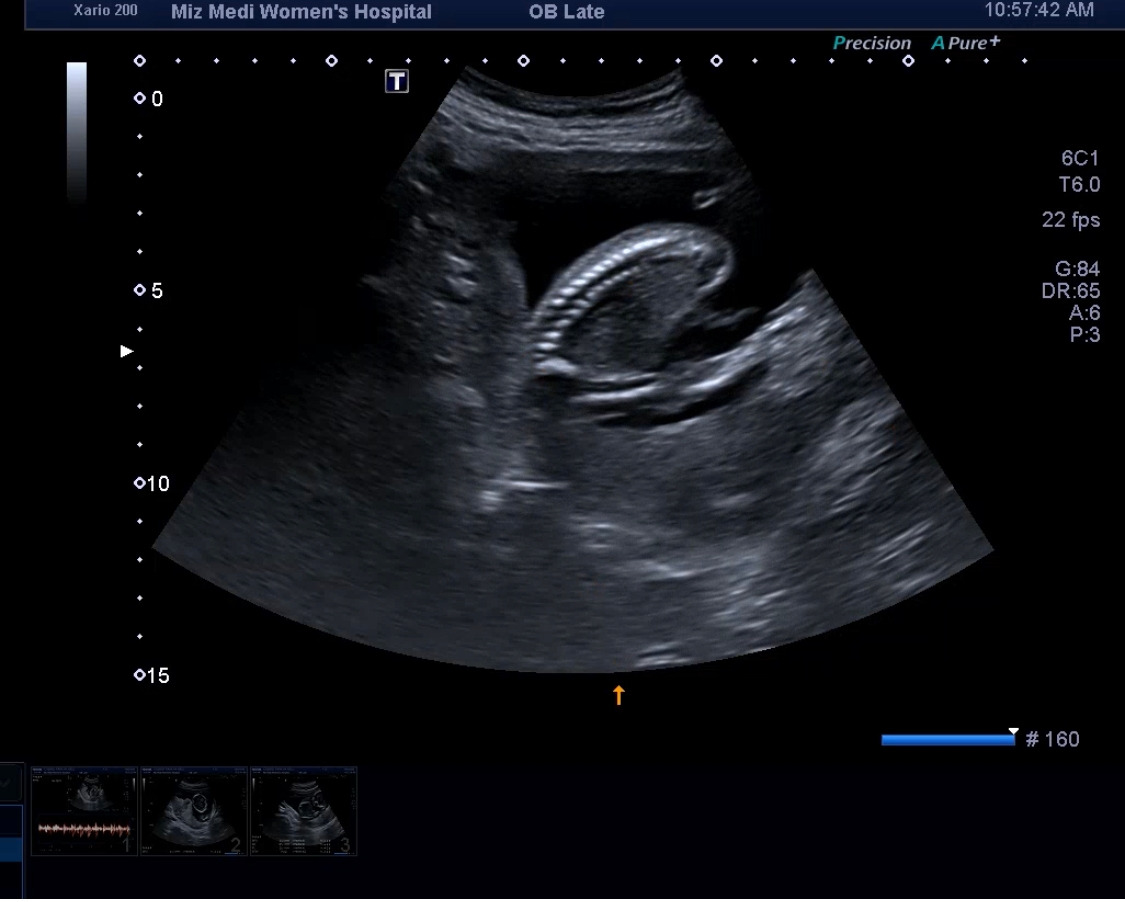

16주차 닭다리컷.jpg

16주 차 치킨컷 너무나 생닭 모양이라 웃었다. 다올아 미안..

이제 아가가 커서 한 컷에 전체 모습을 담기가 어렵더라.

16주차 다리.jpg